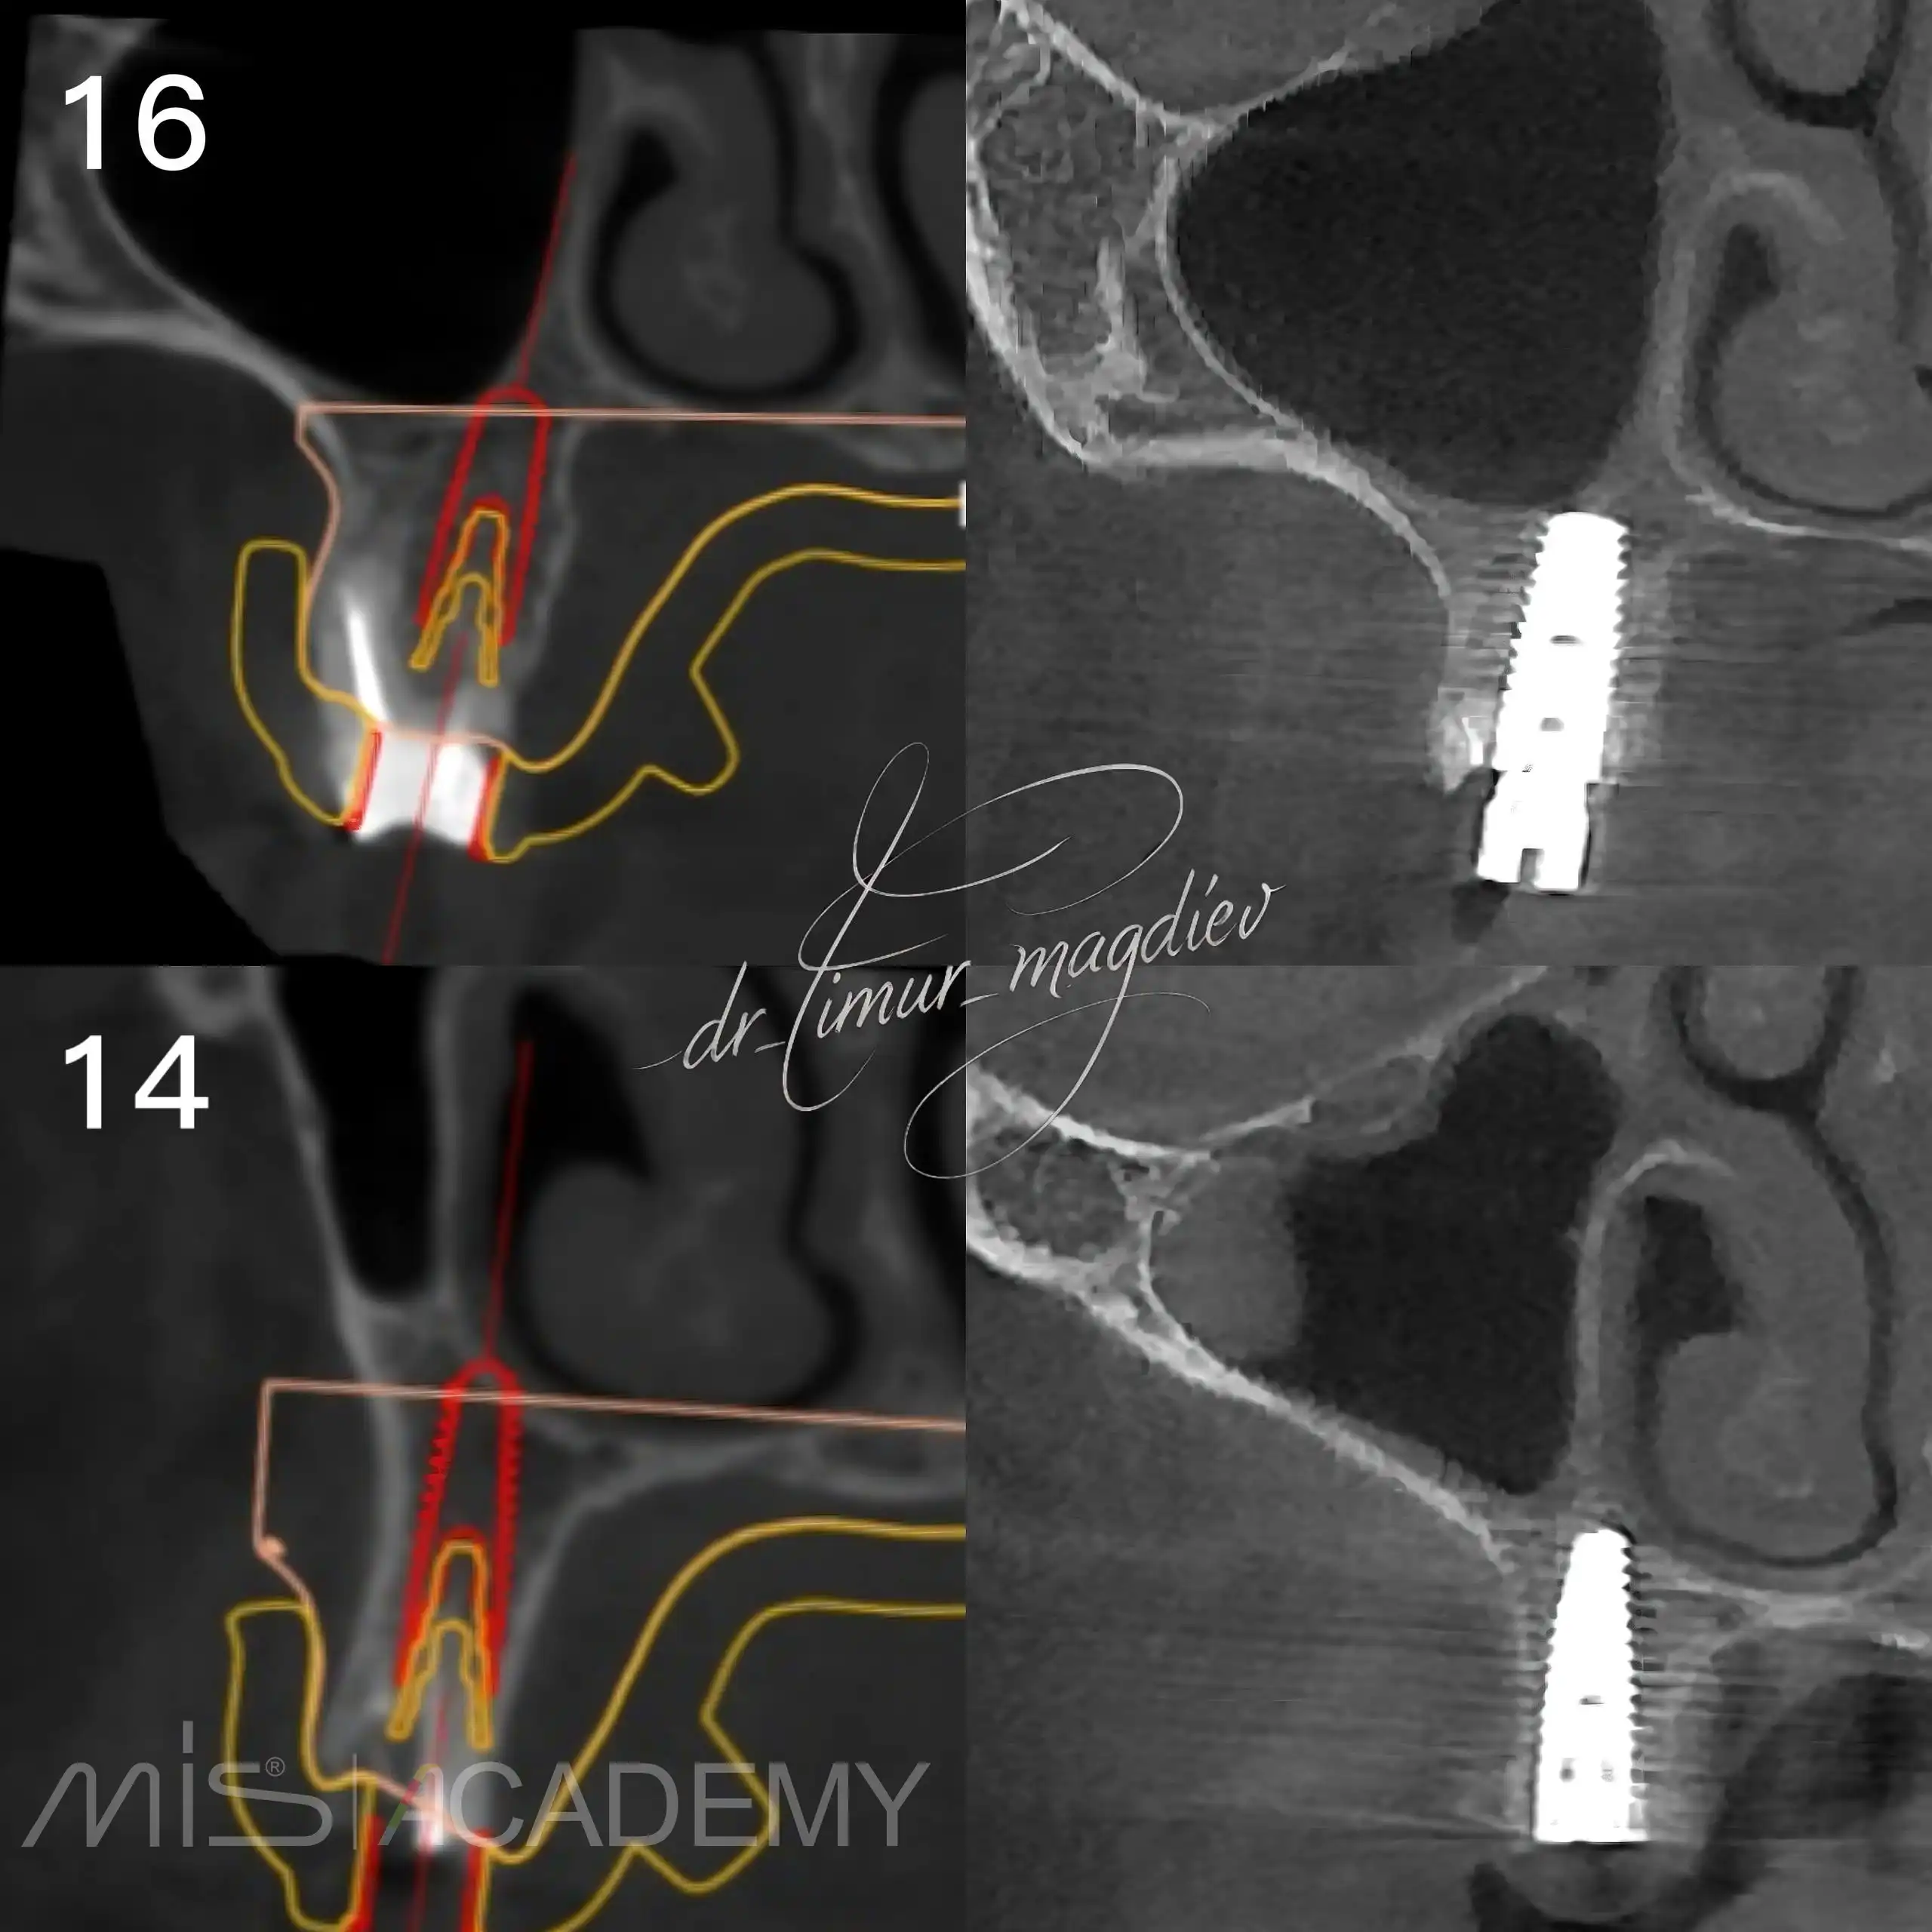

Комплексная реабилитация пациента; в полном навигационном протоколе:

— Установлены имплантаты MIS C1 + Connect абатменты.